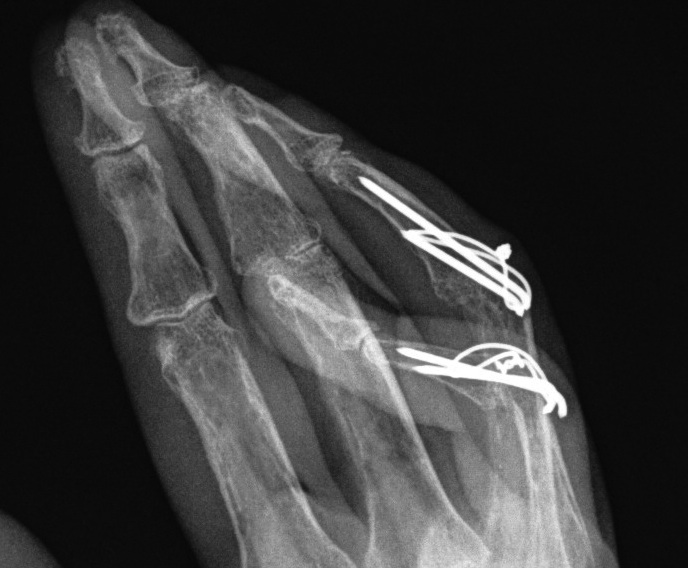

B. Zancoli lateral band transfer

Lateral bands mobilised volar to axis of PIPJ

- raise flap of flexor retinaculum

- suture over lateral band to fix in place

- dorsal blocking splint / K wire

+ DIPJ fusion

PIPJ release first / Lateral band tenolysis / K wire

- release central slip / dorsal capsule / collateral ligs to allow flexion to >90o

- manipulate joint to flexed position

- fix with K-wire